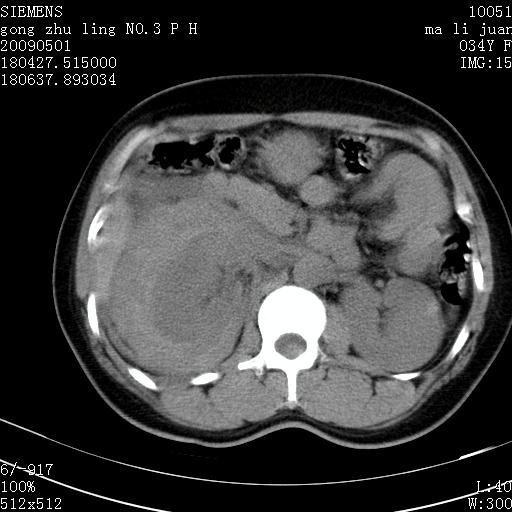

标题: CT19733:右肾碎裂 [打印本页]

标题: CT19733:右肾碎裂

青年女性,骑摩托车摔伤。

右肾碎裂伤,包膜下血肿。

术中仅见右肾碎裂,肾蒂血管未见断裂。

支持右肾碎裂伤,包膜下血肿。

支持右肾破裂伴包膜下血肿。